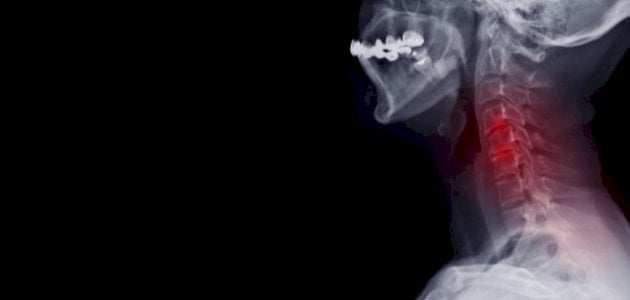

علاج الانزلاق الغضروفي في الرقبة

عمون - يوجد العديد من التدابير المنزلية التي يمكن اتخاذها لتخفيف ألم الانزلاق الغضروفي في الرقبة. هنا بعض الإرشادات المهمة: